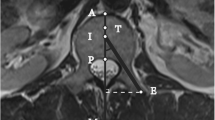

On CT images, leakage was found in 33 of 52 vertebrae, with most frequent localization being paravertebral (50%). The findings on CT and rotational images agreed for the assessment in 30 vertebrae (Fig. 1). Five leakages detected on CT were missed (false negative) on images obtained by rotational acquisition and four were false positive detected with 3D rotational acquisition. Sensitivity and specificity for detecting the leakages with the 3D rotational image acquisition were 0.86 and 0.82, respectively. In all cases, missed extravasations of cement were extremely small, and after analysis of the CT images, re-evaluation of the rotational images using the MIP display and thin slabs disclosed the leakage site (Fig. 2). Clinical symptons caused by the paravertebral leakage were recognized in only one patient with a transient radiculopathy. This leakage was readily detected (Fig. 1). False-positive results of cement leakage on rotational images were in all cases due to the fact that minimal amounts of cement were regarded not to be confined by bone, although on CT, cortical bone structures were detected (Fig. 3).

In all cases, the MIP slabs were regarded to be the best display technique to assess implant distribution. However, even with this image display technique, the assessment of implant distribution within focal lesions was found to be superior on CT images in all cases.